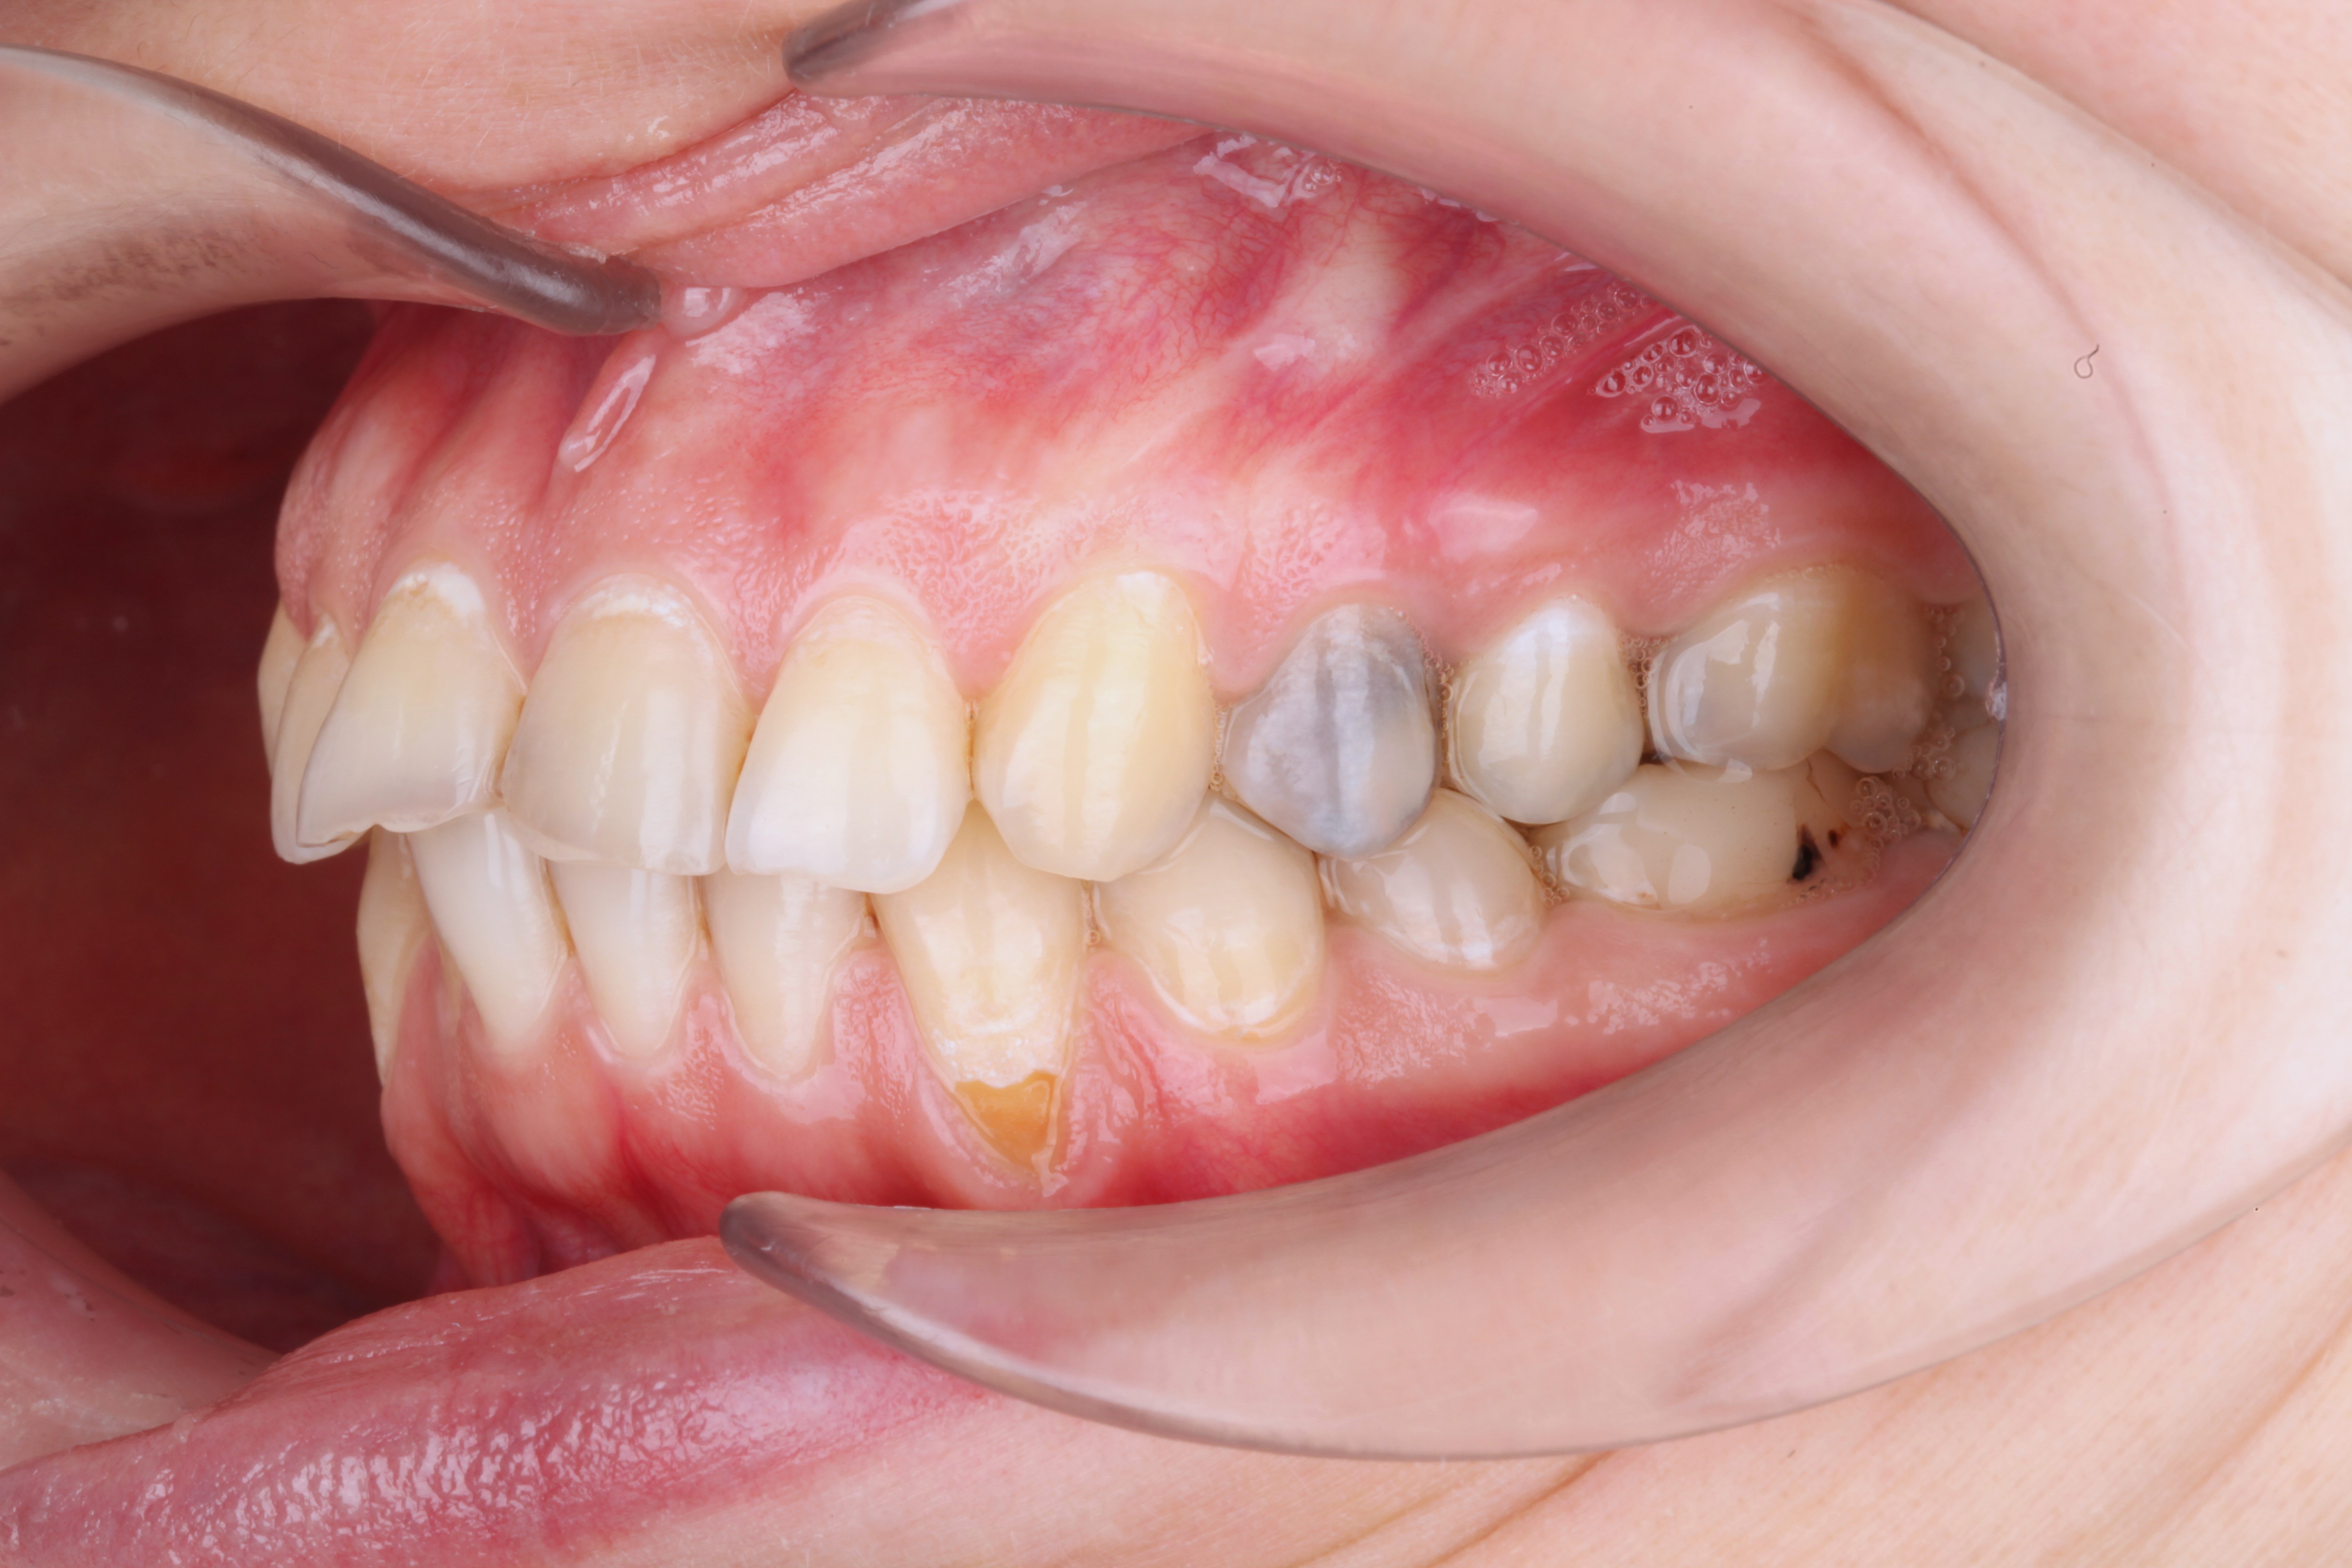

К нам обратилась пациентка 27 лет с желанием сделать красивую улыбку с ровными и красивыми зубами. На фотографии мы видим выраженные рецессии десны на нижних клыках, несостоятельные пломбы, скученность и стираемость.

В данной клинической ситуации было принято решение провести санацию полости рта, затем закрыть рецессии в области нижних клыков и только потом приступить к ортодонтии.